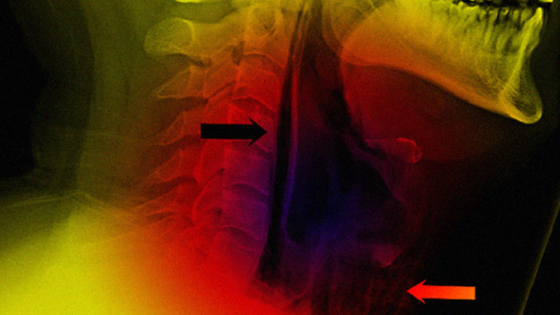

Неприятность случилась с 34-летним мужчиной. Он обратился в больницу с жалобами на острую боль при глотании и изменение голоса. По словам пациента, симптомы появились после того, как он попытался остановить чих, зажав нос и рот руками. Остановить рефлекс не получилось, но после он заметил, как опухла шея.

Рентген снимок показал, что у мужчины спонтанный разрыв пищевода.